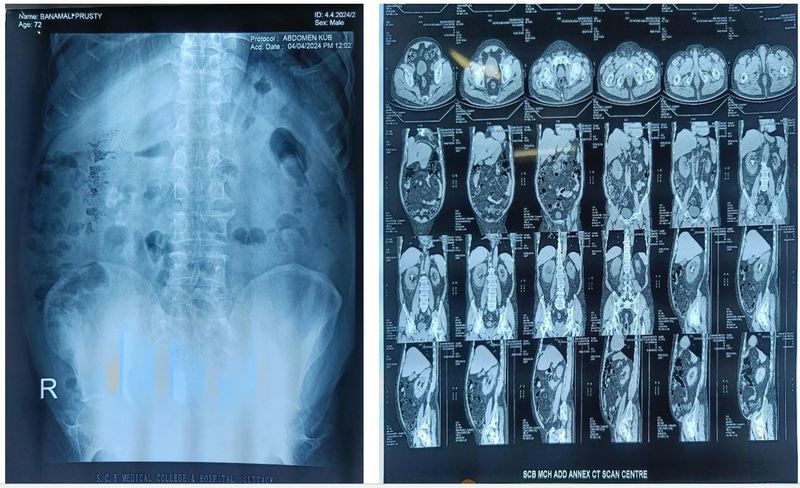

Case of Hypervitaminosis presenting a renal calculus

A 72-year-old diabetic male presented with fever for 5 days, with burning micturition and pain in the lower abdomen associated with urgency and hesitancy. On examination of urine, it showed pus cells, USG showed bilateral renal Calculi, and x-ray KUB also showed the same on metabolic evaluation serum calcium was raised, se vit D3 level was 200 ng/mL. on retrograde questioning, the patient was found to have a history of long-term intake of calcium+ D3 tablets.